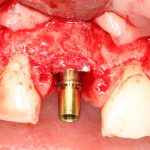

Рекомендации по установке имплантов. Для всех. Часть V.